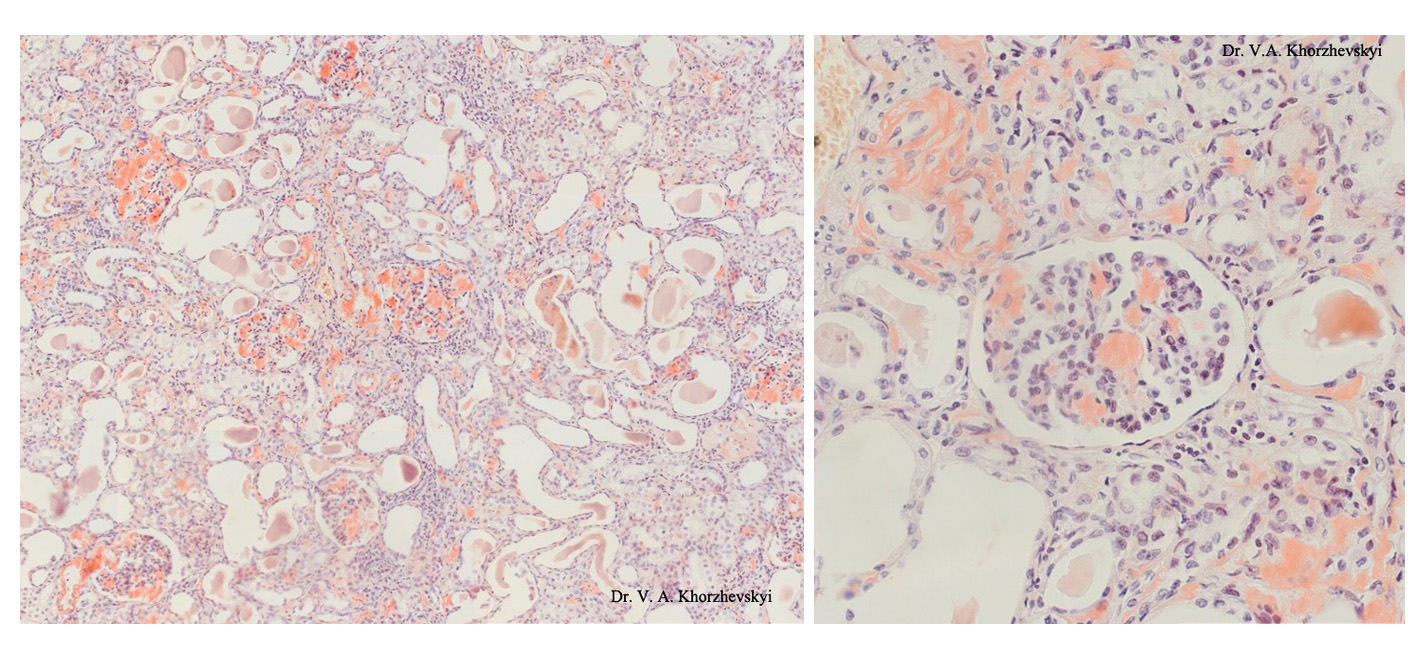

Карнификация Легкого: Микропрепараты и Диагностика

Раздел: Калейдоскоп образов